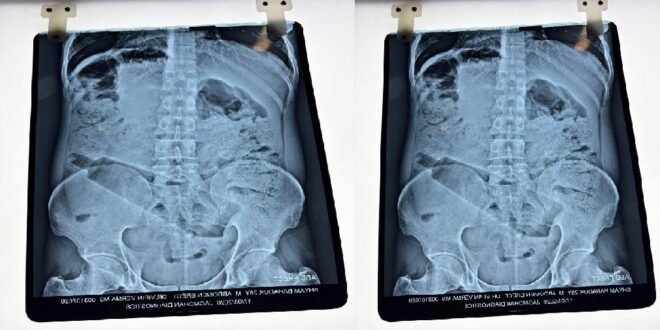

डॉक्टरों ने इस मामले में ऑपरेशन करके पेट से प्लास्टिक की बोतल निकाली है…बता दें कि इस तरीके का मामला कुछ दिन पहले आगरा से भी सामने आया था…जहां पर युवक ने अपने प्राइवेट पार्ट में बोतल डाल ली थी…